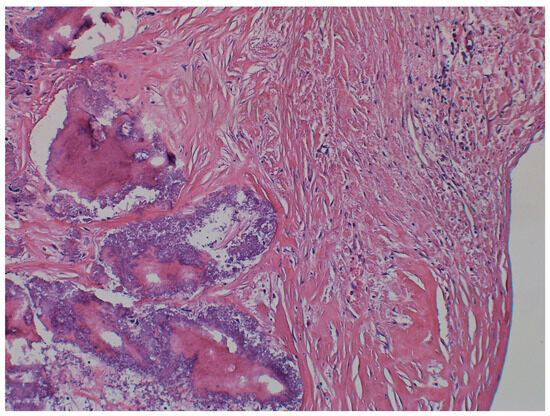

| 5. Fukushima et al., 2022 [3] | 80, F | History of GPA | Nodules of calcification and fibroblasts; CAT | Anterior mitral leaflet | Surgical resection |